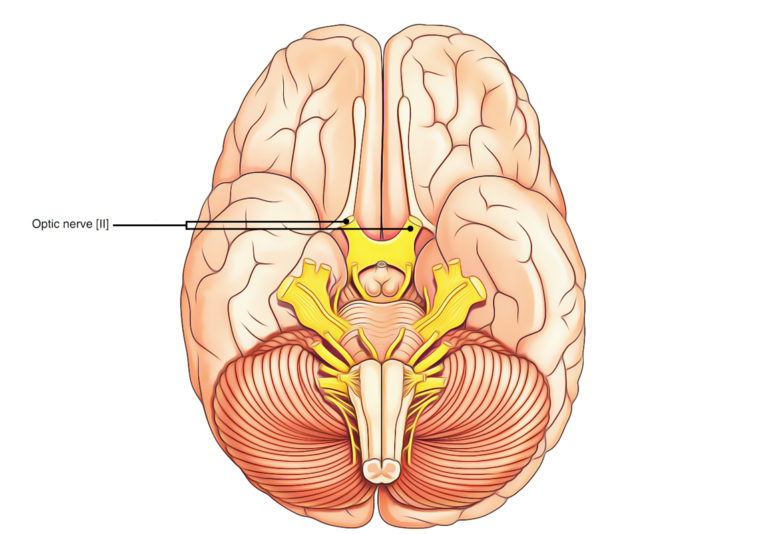

Optic Nerve In Eye. For this reason, the optic nerve is also called the second cranial nerve or cranial nerve ii. the optic nerve, also known as the cranial nerve ii, is a bundle of nerve fibers that carry visual information from. The optic nerve is located in the back of the eye. It’s comprised of four parts: Learn about its structure, role, and common diseases that can affect it and cause vision problems. the optic nerve is a bundle of nerve fibers that transmits visual information from the eye to the brain. the optic nerve is the nerve that carries information from the eye to the brain. one of the most important nerves in the upper body, the optic nerve connects the eyeball and the brain. It’s responsible for carrying messages between the eye and brain. It’s the second of 12 cranial nerves, which include the olfactory nerve, oculomotor nerve, facial nerve and others. It is also called the second cranial nerve or. Intraocular, intraorbital, intracanalicular, and intracranial.

The optic nerve is located in the back of the eye. It’s comprised of four parts: the optic nerve is the nerve that carries information from the eye to the brain. It is also called the second cranial nerve or. Learn about its structure, role, and common diseases that can affect it and cause vision problems. It’s responsible for carrying messages between the eye and brain. It’s the second of 12 cranial nerves, which include the olfactory nerve, oculomotor nerve, facial nerve and others. For this reason, the optic nerve is also called the second cranial nerve or cranial nerve ii. the optic nerve, also known as the cranial nerve ii, is a bundle of nerve fibers that carry visual information from. the optic nerve is a bundle of nerve fibers that transmits visual information from the eye to the brain.

Optic Nerve In Eye It’s the second of 12 cranial nerves, which include the olfactory nerve, oculomotor nerve, facial nerve and others. It is also called the second cranial nerve or. It’s responsible for carrying messages between the eye and brain. For this reason, the optic nerve is also called the second cranial nerve or cranial nerve ii. the optic nerve is a bundle of nerve fibers that transmits visual information from the eye to the brain. one of the most important nerves in the upper body, the optic nerve connects the eyeball and the brain. The optic nerve is located in the back of the eye. Intraocular, intraorbital, intracanalicular, and intracranial. It’s the second of 12 cranial nerves, which include the olfactory nerve, oculomotor nerve, facial nerve and others. the optic nerve, also known as the cranial nerve ii, is a bundle of nerve fibers that carry visual information from. It’s comprised of four parts: Learn about its structure, role, and common diseases that can affect it and cause vision problems. the optic nerve is the nerve that carries information from the eye to the brain.